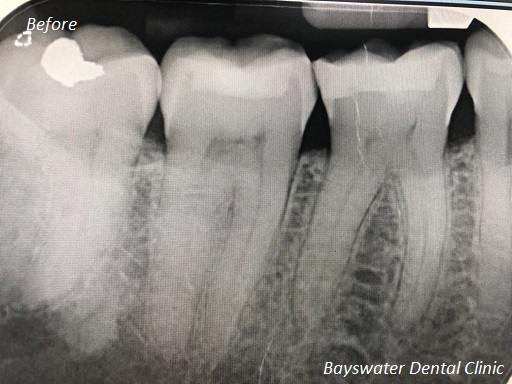

Root Canal Treatment on a molar teeth which had deep decay!

before

after